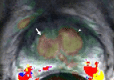

Purpose: To analyze the diffusion and perfusion parameters of central gland (CG) prostate cancer, stromal hyperplasia (SH), and glandular hyperplasia (GH) and to determine the role of these parameters in the differentiation of CG cancer from benign CG hyperplasia.

Materials and methods: In this institutional review board-approved (with waiver of informed consent), HIPAA-compliant study, 38 foci of carcinoma, 38 SH nodules, and 38 GH nodules in the CG were analyzed in 49 patients (26 with CG carcinoma) who underwent preoperative endorectal magnetic resonance (MR) imaging and radical prostatectomy. All carcinomas and hyperplastic foci on MR images were localized on the basis of histopathologic correlation. The apparent diffusion coefficient (ADC), the contrast agent transfer rate between blood and tissue (K(trans)), and extravascular extracellular fractional volume values for all carcinoma, SH, and GH foci were calculated. The mean, standard deviation, 95% confidence interval (CI), and range of each parameter were calculated. Receiver operating characteristic (ROC) and multivariate logistic regression analyses were performed for differentiation of CG cancer from SH and GH foci.

Results: The average ADCs (× 10(-3) mm(2)/sec) were 1.05 (95% CI: 0.97, 1.11), 1.27 (95% CI: 1.20, 1.33), and 1.73 (95% CI: 1.64, 1.83), respectively, in CG carcinoma, SH foci, and GH foci and differed significantly, yielding areas under the ROC curve (AUCs) of 0.99 and 0.78, respectively, for differentiation of carcinoma from GH and SH. Perfusion parameters were similar in CG carcinomas and SH foci, with K(trans) yielding the greatest AUCs (0.75 and 0.58, respectively). Adding K(trans) to ADC in ROC analysis to differentiate CG carcinoma from SH increased sensitivity from 38% to 57% at 90% specificity without noticeably increasing the AUC (0.79).

Conclusion: ADCs differ significantly between CG carcinoma, SH, and GH, and the use of them can improve the differentiation of CG cancer from SH and GH. Combining K(trans) with ADC can potentially improve the detection of CG cancer.